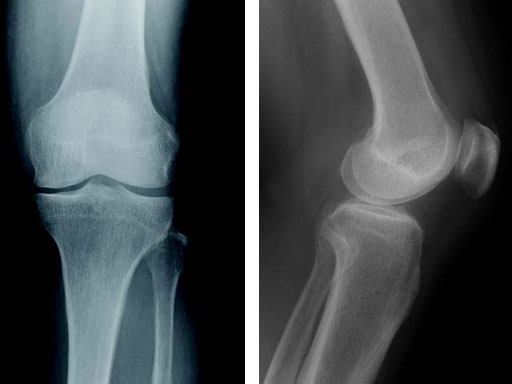

65-year-old female. Osteoarthritic patient complaining of medial knee pain of her left knee.

Case provided by Takeshi Sawaguchi, Toyama, JP